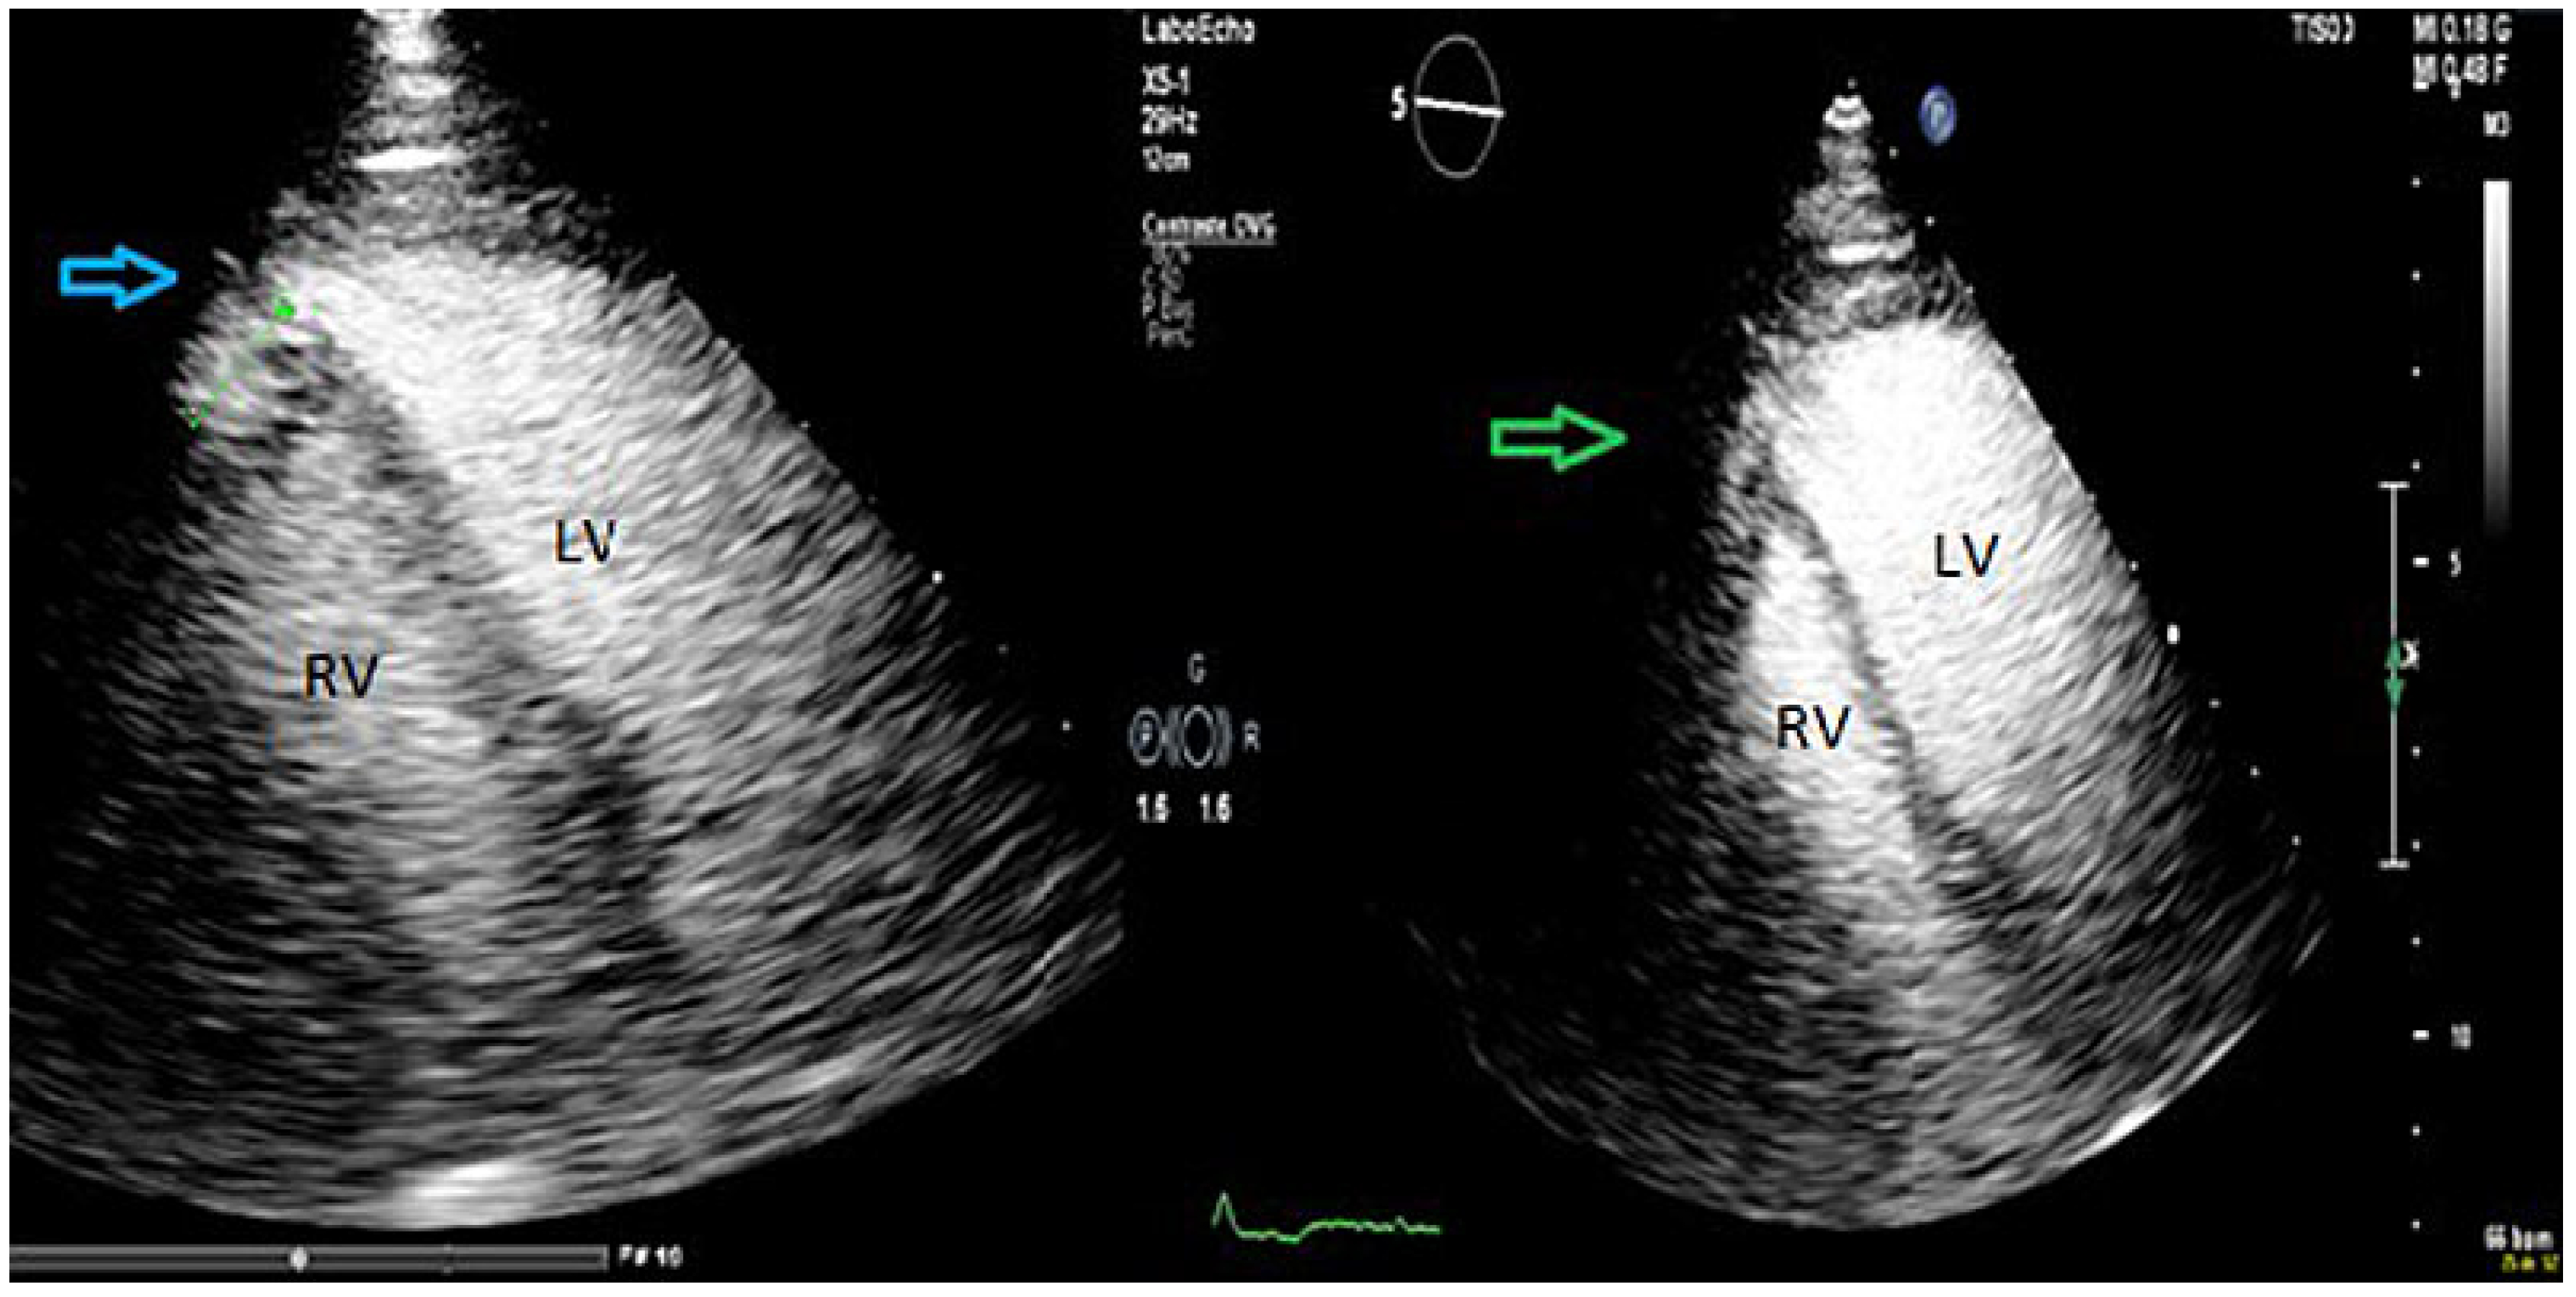

Two months after the intervention the patient was admitted for further work-up. Clinical examination was normal. The electrocardiogram (ECG) showed sinus rhythm, with normal axis and right bundle branch block. The laboratory findings, including high sensitive troponin I, were normal. At transthoracic echocardiography, the left ventricle was normal sized, with no evidence of ventricular septal defects (Figure 2). Injection of transpulmonary echocardiographic contrast agent (SonoVue, Bracco Suisse SA, Swissmedic, Manno, Switzerland) confirmed the presence of a small apical cavity with a 6 mm neck localised at the septo-apical level with extension under the apex of the right ventricle. The walls of this cavity showed a trabecular appearance with preserved contractility. There was a systolic expansion of a maximum length of 15 mm, without evidence of communication between the two ventricles on colour and pulsed-wave Doppler.

Figure 2. Transthoracic echocardiography showed cavity expansion in systole (blue arrow) and size reduction during diastole (green arrow). LV = left ventricle; RV = right ventricle.